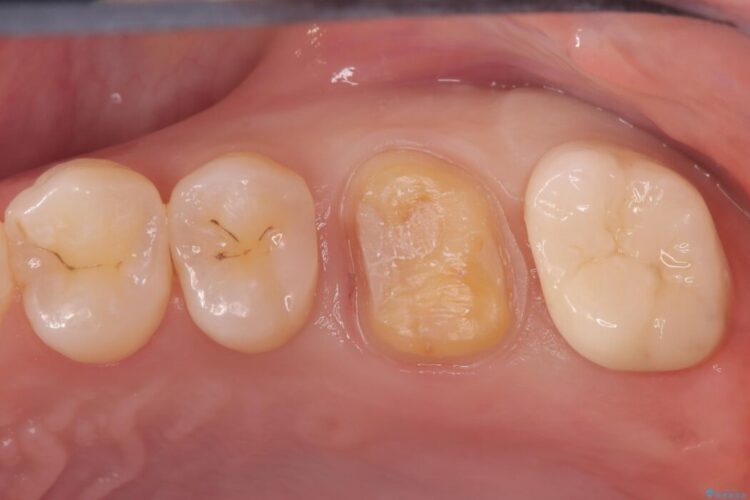

経過観察と土台作り: 一定期間の経過を観察し、痛みや炎症がないことを確認。神経の生存を確認した上で、セラミックを支えるための土台を精密に構築しました。

セラミックによる修復: 最終的な補綴物にはセラミックを使用しました。高い適合性により、二次的な虫歯のリスクを抑えつつ、天然歯のような自然な咬み心地と美しさを再現しました。